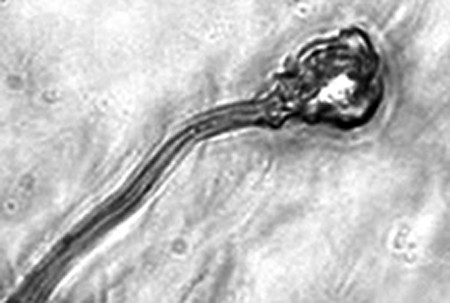

据报告的主要作者卡里姆教授介绍,这种试管培育精子(IVDsperm)与人类自然产生的精子并不完全一样,但两者拥有4个重要的相似点:它们包含有23个染色体;有精子那样的头和尾巴;有可以使卵细胞受精的蛋白质;它们也可以像天然精子一样游动。